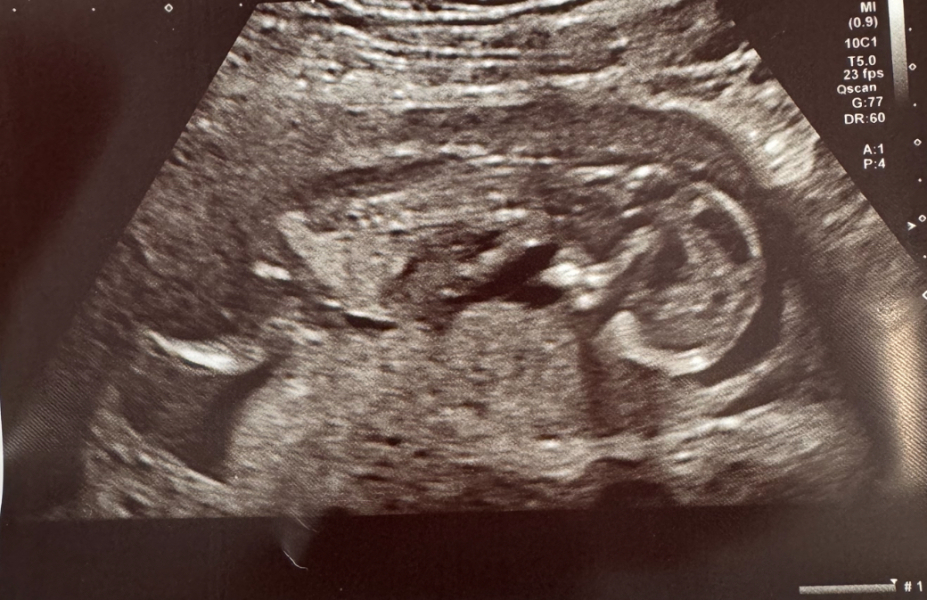

Forgot to share scan sorry - baby rolled over for the pics ha! Tbh our scan pics at private clinic last week were better as today baby was very active!! But is nice to keep for each stage!

@Khanga27 ahahah, it’s so funny I have never seen a baby facing downwards like this 😂 I wonder if they were hiding from having their picture taken 😂 you know like an ostrich.

@Xur i know, it’s quite funny!! It made me very glad we got the private pictures and video last week to be honest ha. I couldn’t believe how much movement/dancing was going on in there, was like a party in my tummy 😂

@MudandMoet so mine was actually on back for measurements, but there were one or two that took a little longer, then it was when she was doing pics at end that baby rolled onto front 😂 very active!